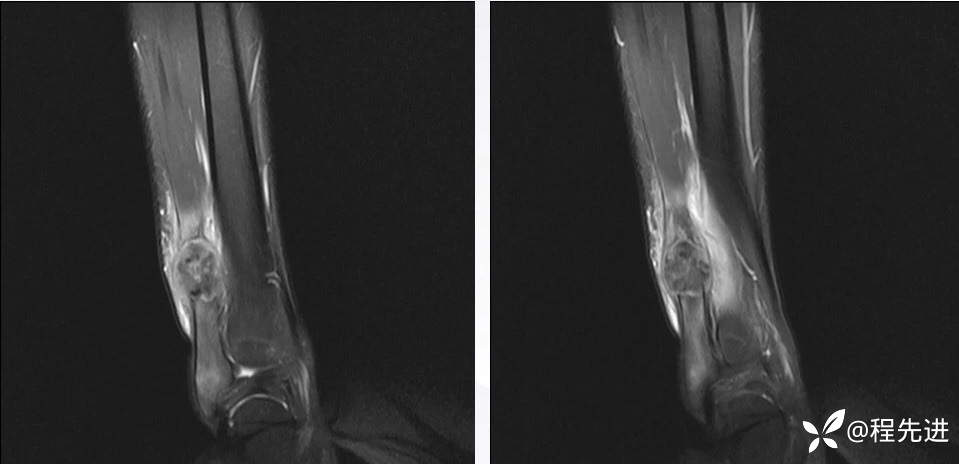

MR

T2

T1

T1+C